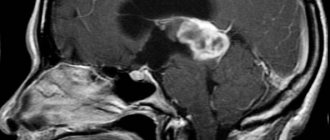

Шишковидное тело, которое также носит название эпифиз (epiphysis cerebri), это небольшое образование, напоминающее по